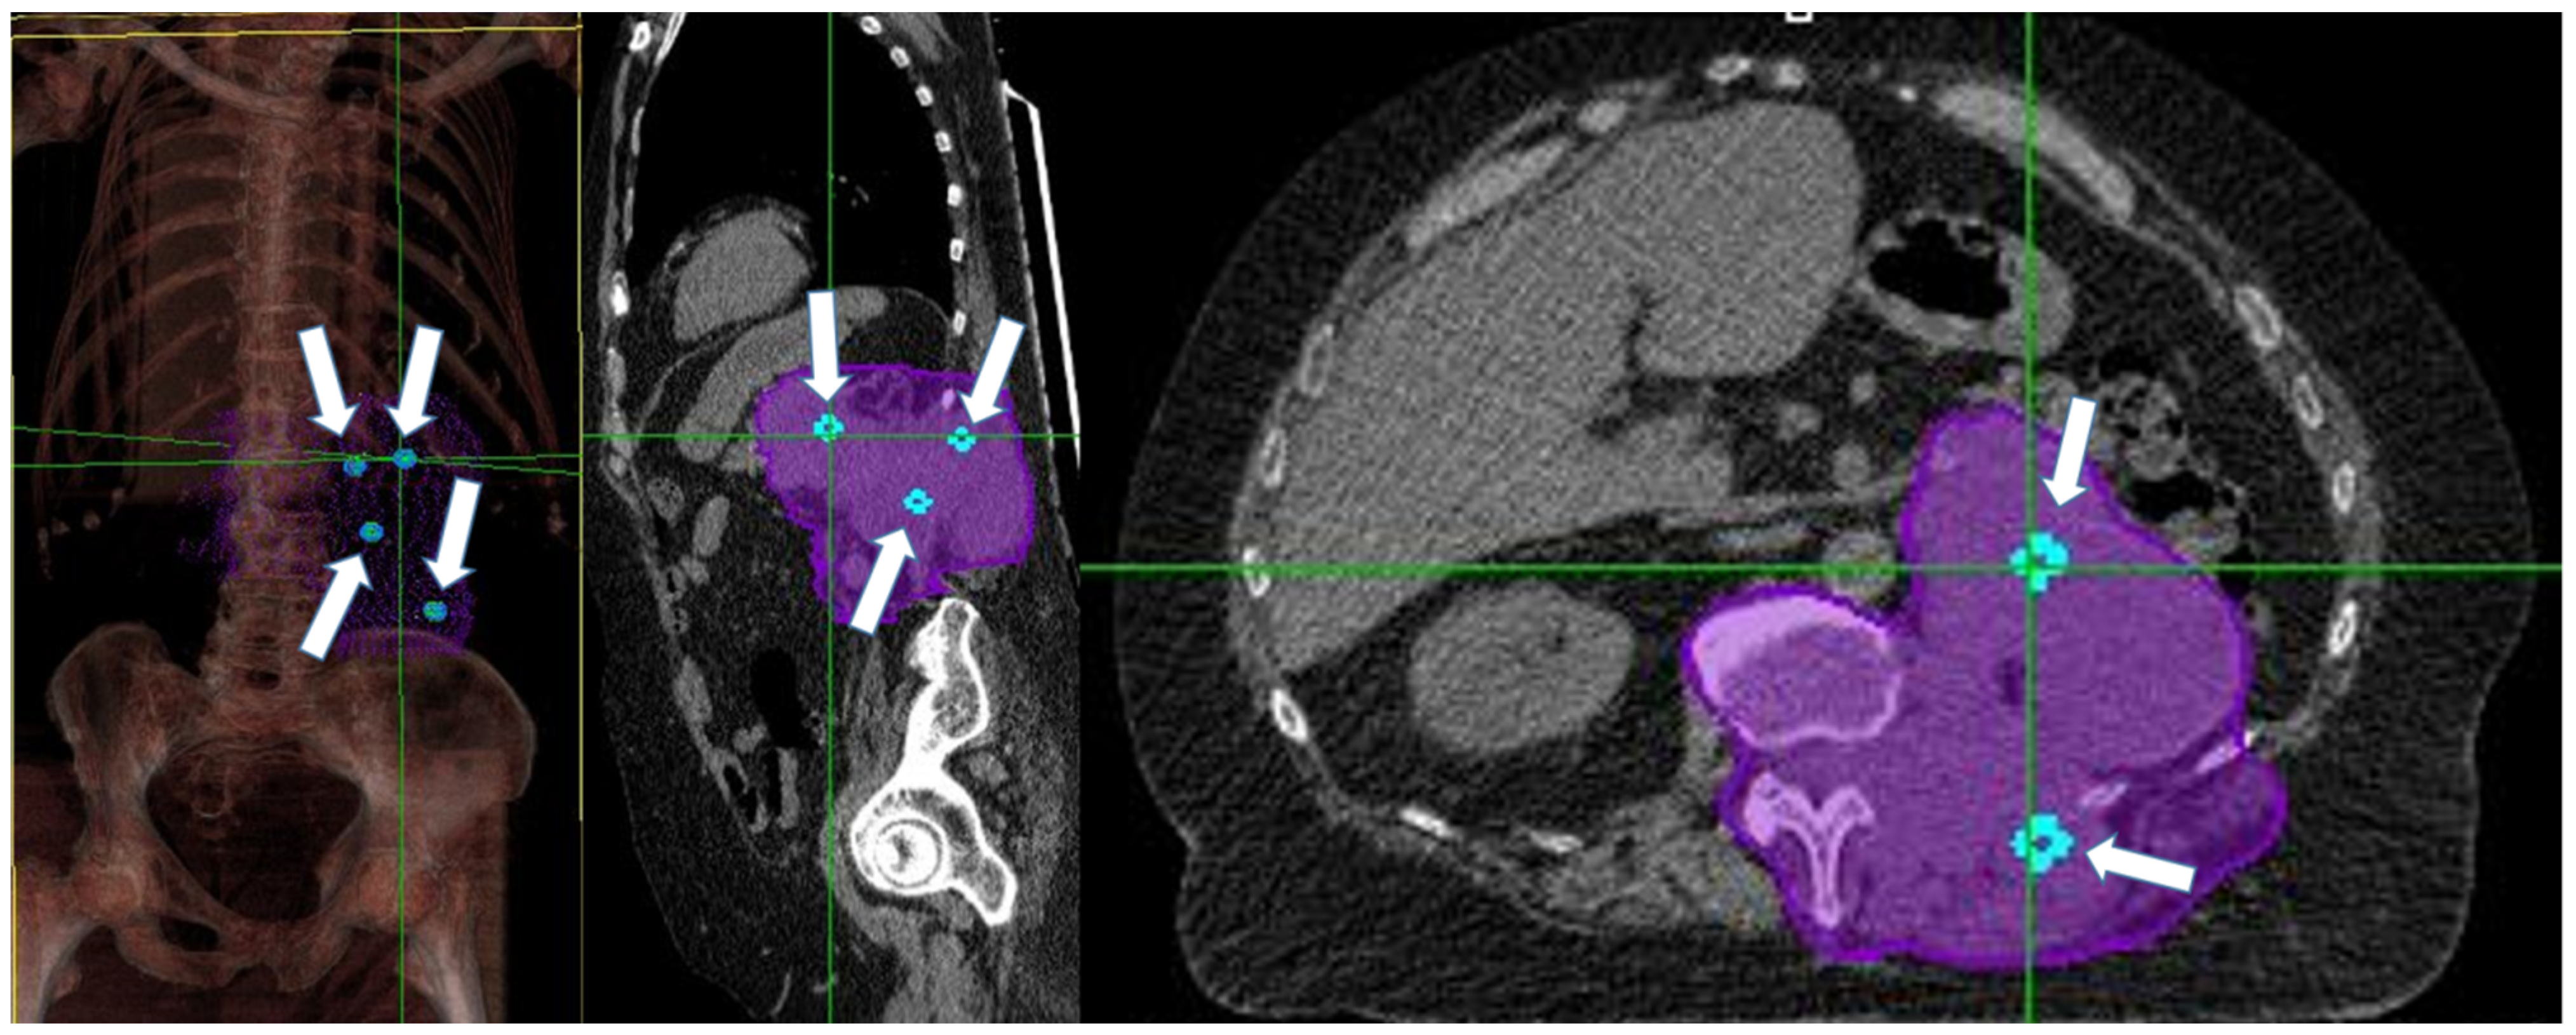

2.2.1. Vertex Positioning and Treatment Planning for Bulky Disease